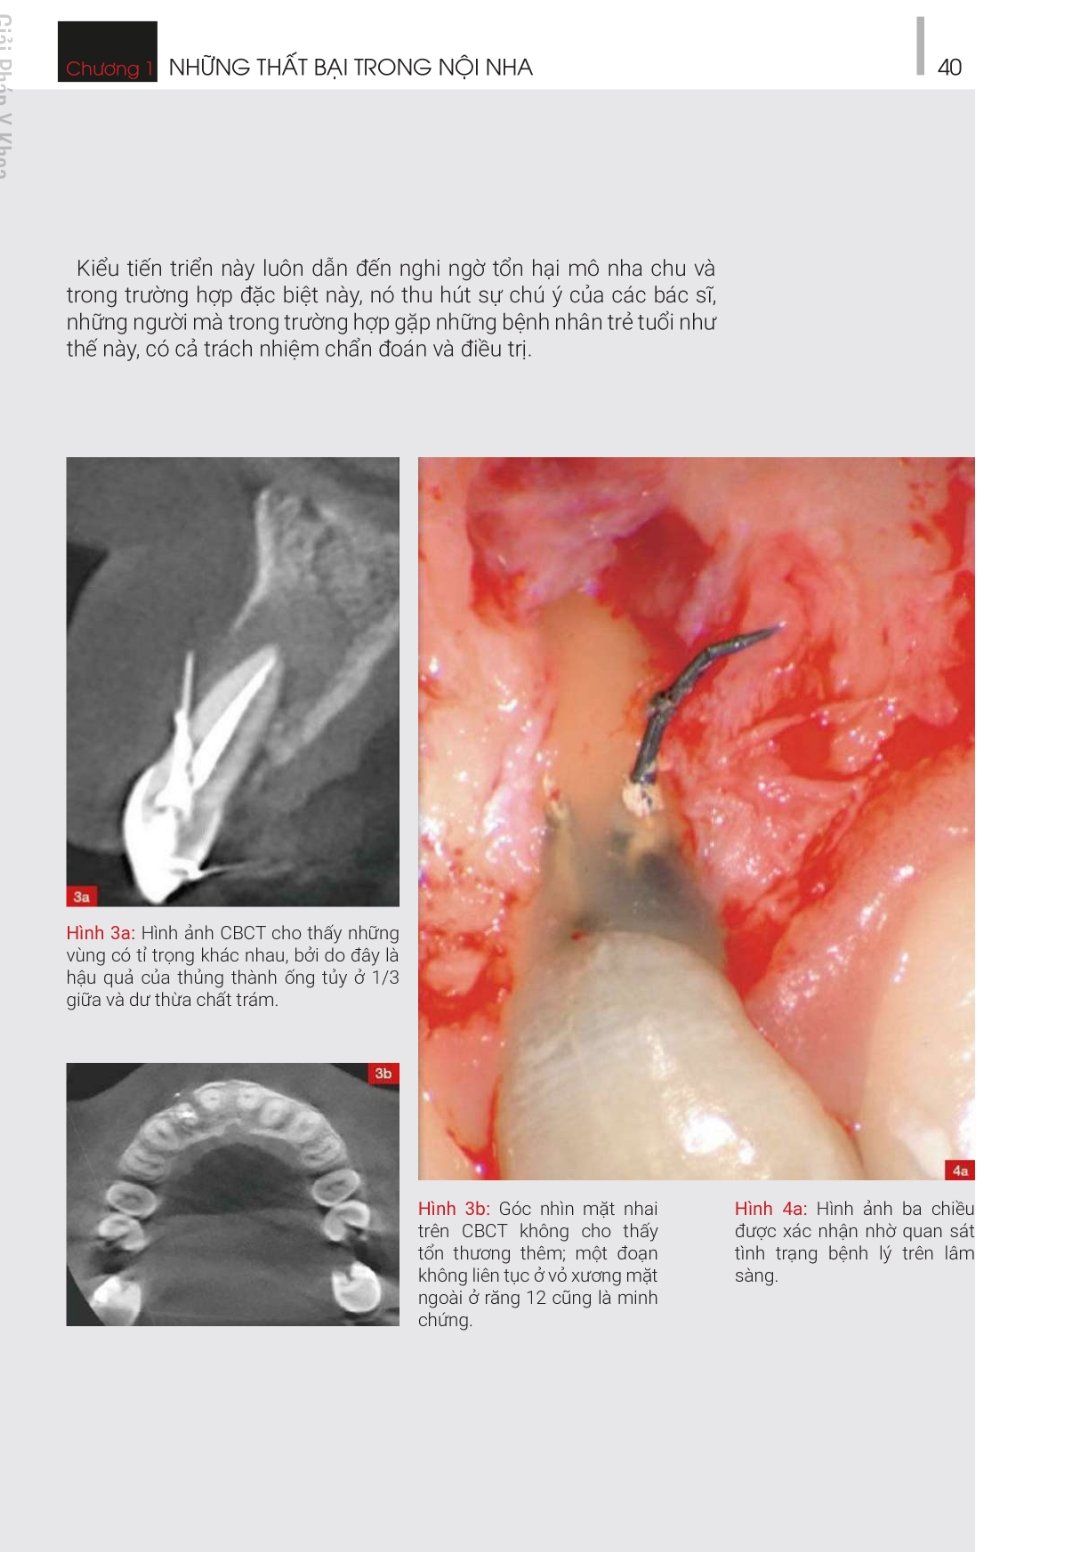

ĐIỀU TRỊ LẠI – NHỮNG GIẢI PHÁP SANG THƯƠNG QUANH CHÓP NGUỒN GỐC TỪ NỘI NHA